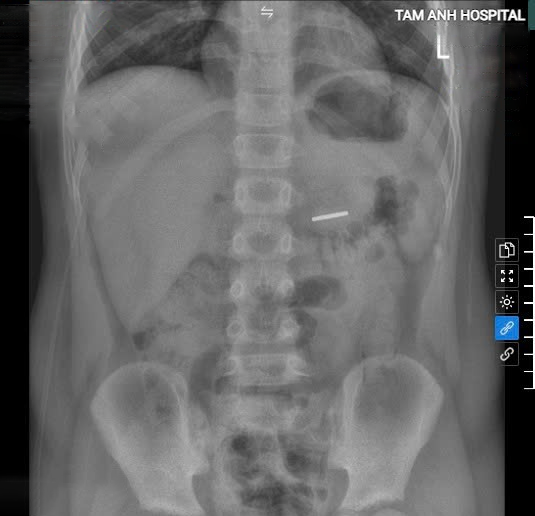

BS.CKI Đinh Xuân Hoàng, khoa Nhi, Bệnh viện Đa khoa Tâm Anh Hà Nội, cho biết bé nhập viện trong trạng thái tỉnh táo, tim phổi bình thường, kết quả chụp X-quang cho thấy có dị vật cản quang kích thước 2,5 cm nằm trong dạ dày. Bác sĩ nội soi gắp một thỏi nam châm màu nâu sẫm tại vị trí tá tràng D3. Sau can thiệp, bé tỉnh táo, xuất viện sau một ngày.